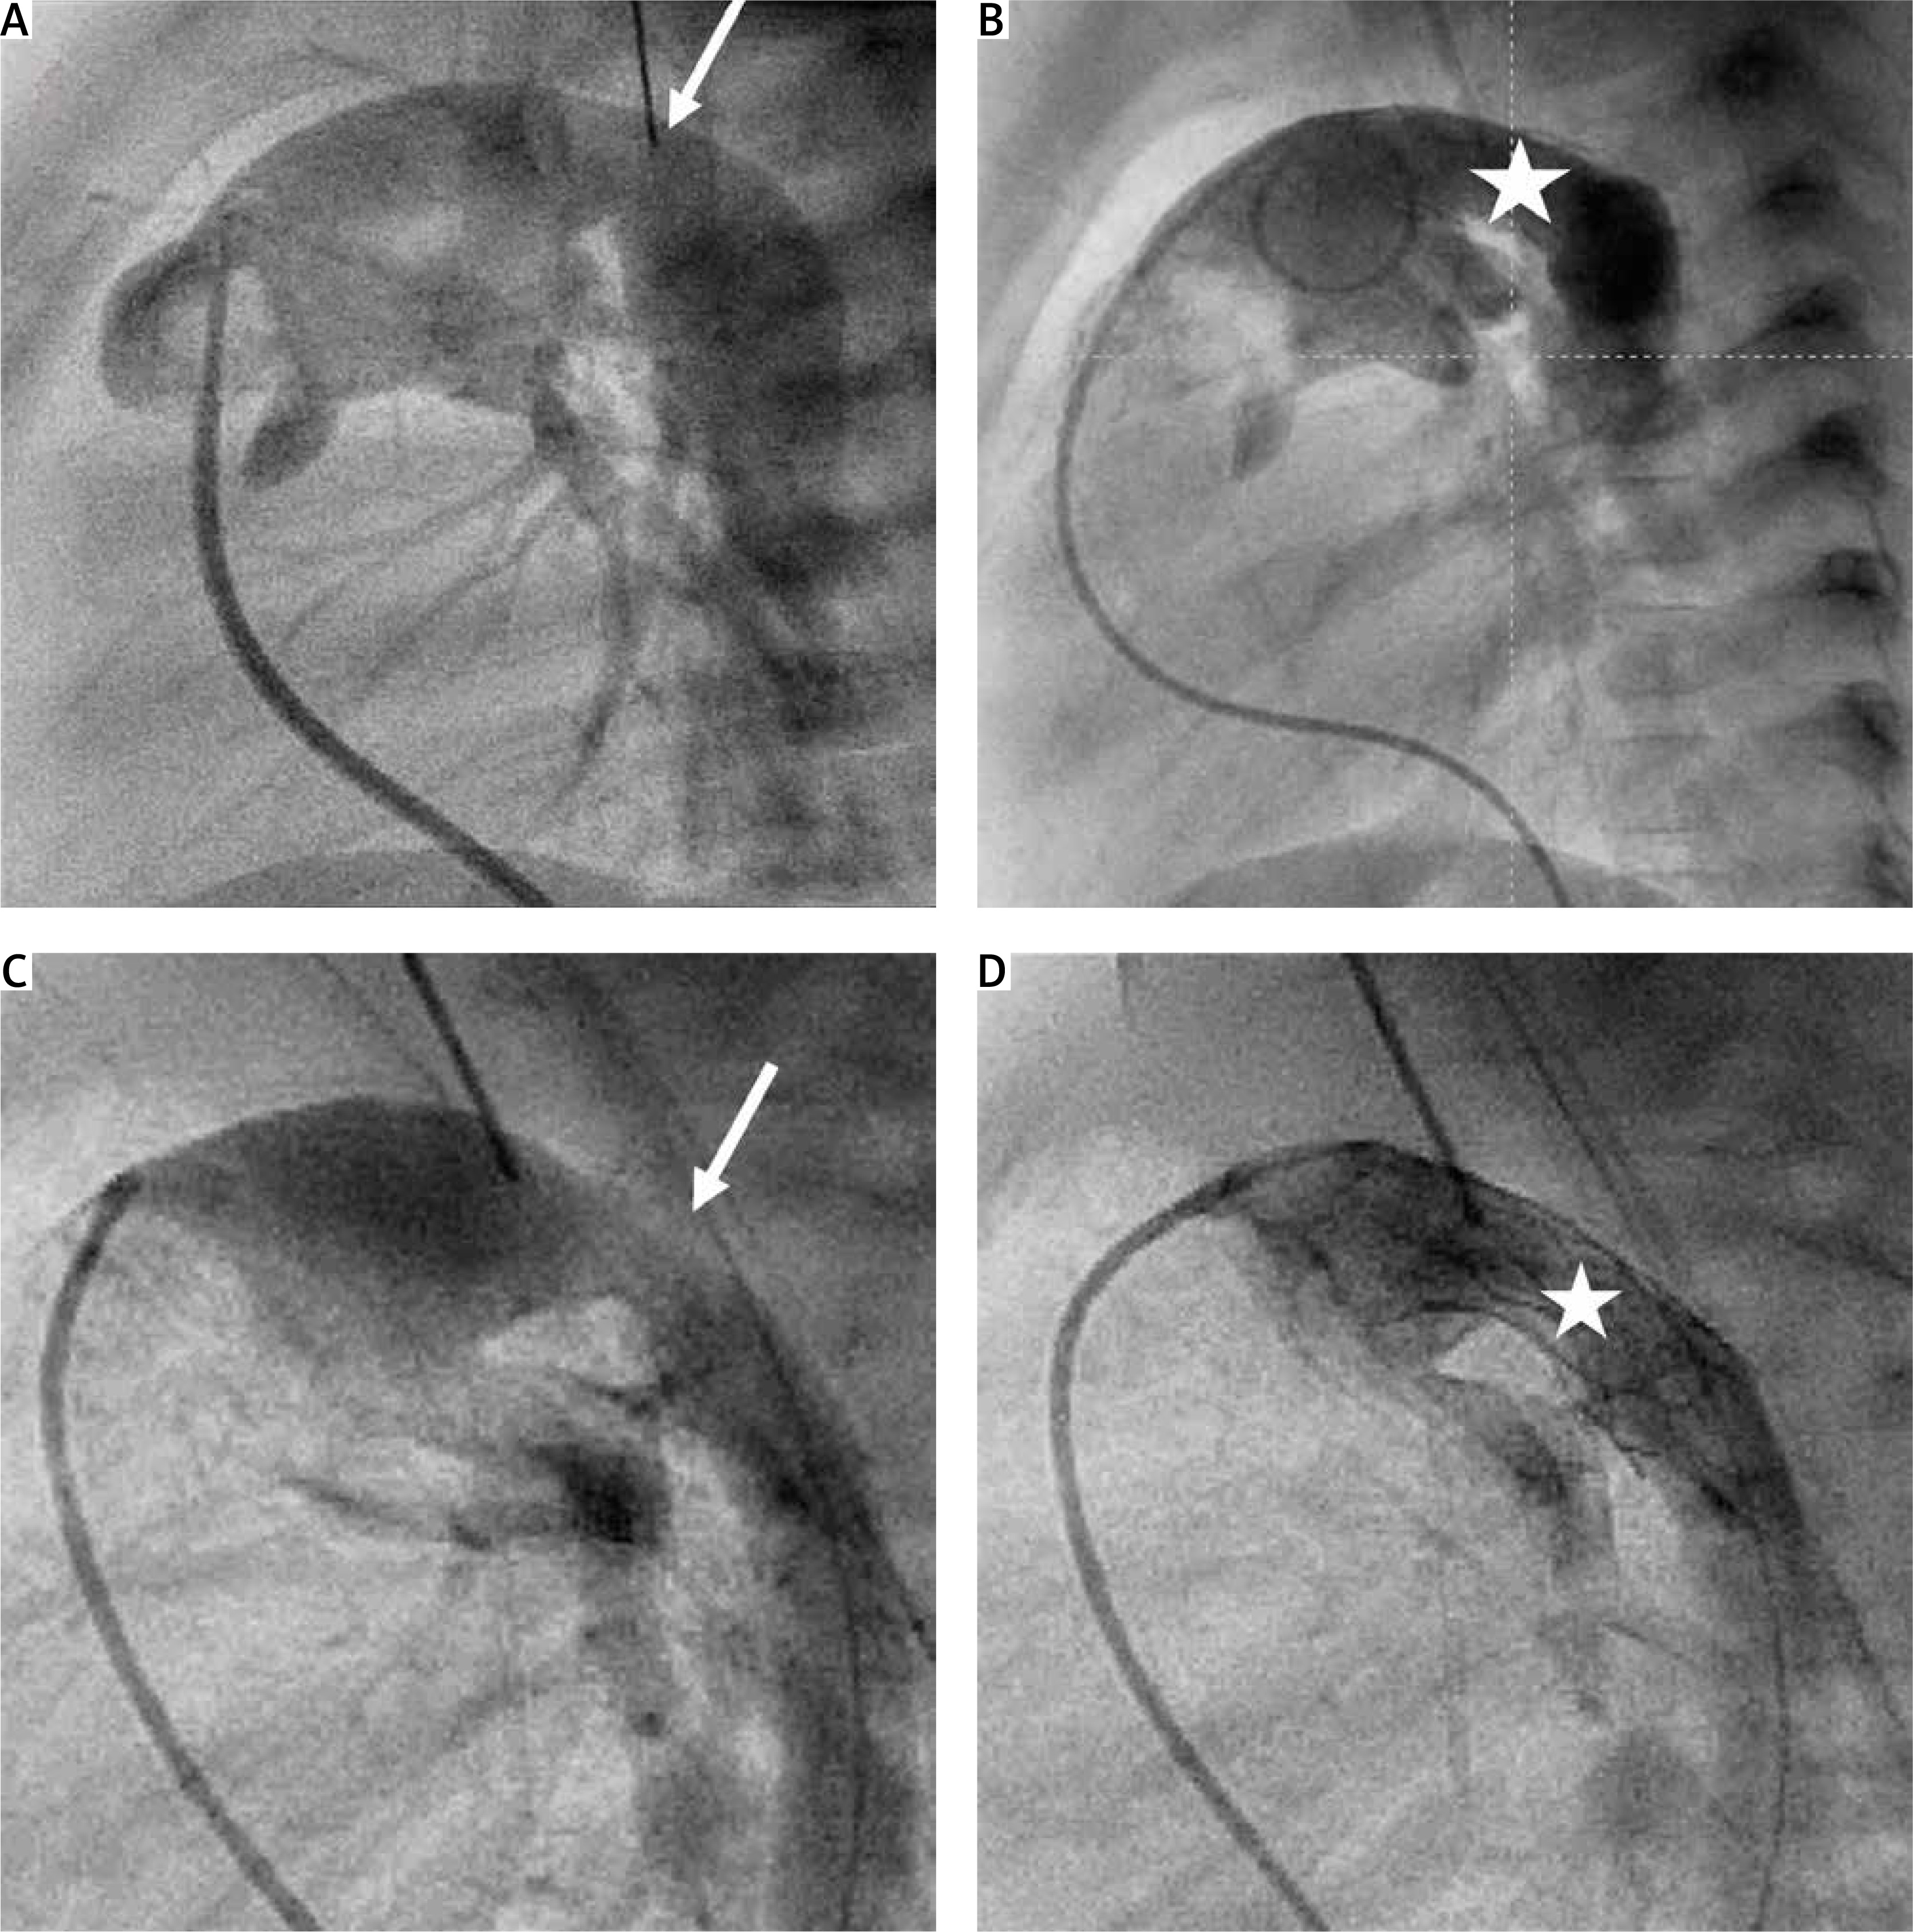

Figure 5

Arterial duct stent dislodgment into the descending aorta. A, B – Pulmonary artery angiography in lateral view showing proximal arterial duct stenosis (white arrows). A stent Palmaz Genesis 8 mm/15 mm deployed in the distal arterial duct. White circle indicates a dislodged stent Palmaz Genesis 7 mm/12 mm following re-dilation. B – Tight pulmonary arteries band (yellow arrow). C – Aortic arch angiography showing extremely hypoplastic ascending aorta (white arrow)